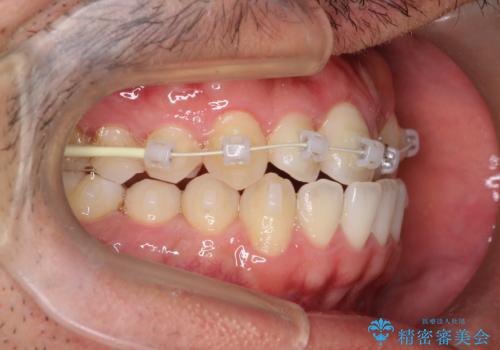

前歯が反対にかんでいる インビザラインとワイヤーを組み合わせた矯正治療

- インビザライン 審美装置

- 前歯が正常とは反対にかんでいるとのことで、来院されました。

患者様がマウスピースを希望されていましたが、上の前歯のがたつきを先にワイヤーで改善する方が早く治療が終了することが可能であるとお伝えし、上顎のみ半年間ワイヤーで治療を行いました。

マウスピースのみでの治療も可能でしたが、治療期間がもう少し延長していた可能性があります。